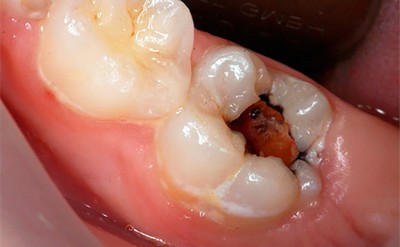

- Запущенный кариес — основная из них. С течением времени без необходимого лечения кариозная полость продолжает расширяться и углубляться, из-за чего патогенные бактерии легко проникают в мягкую зубную ткань. Проникновение происходит как напрямую, если пульпа открыта, так и по дентинным каналам.

В сочетании с пищевыми остатками подобная микрофлора образует налёт.

Микроорганизмы начинают выделять кислоту, остатки пищи разлагаются, и зубная эмаль постепенно разрушается. Образуется кариес, инфекция которого с течением времени проникает в дентин (костное вещество зуба), а затем и в пульпу. В этой мягкой ткани расположено огромное количество нервных окончаний. Отёкшая воспалённая пульпа их сдавливает, что вызывает острую пронизывающую боль.